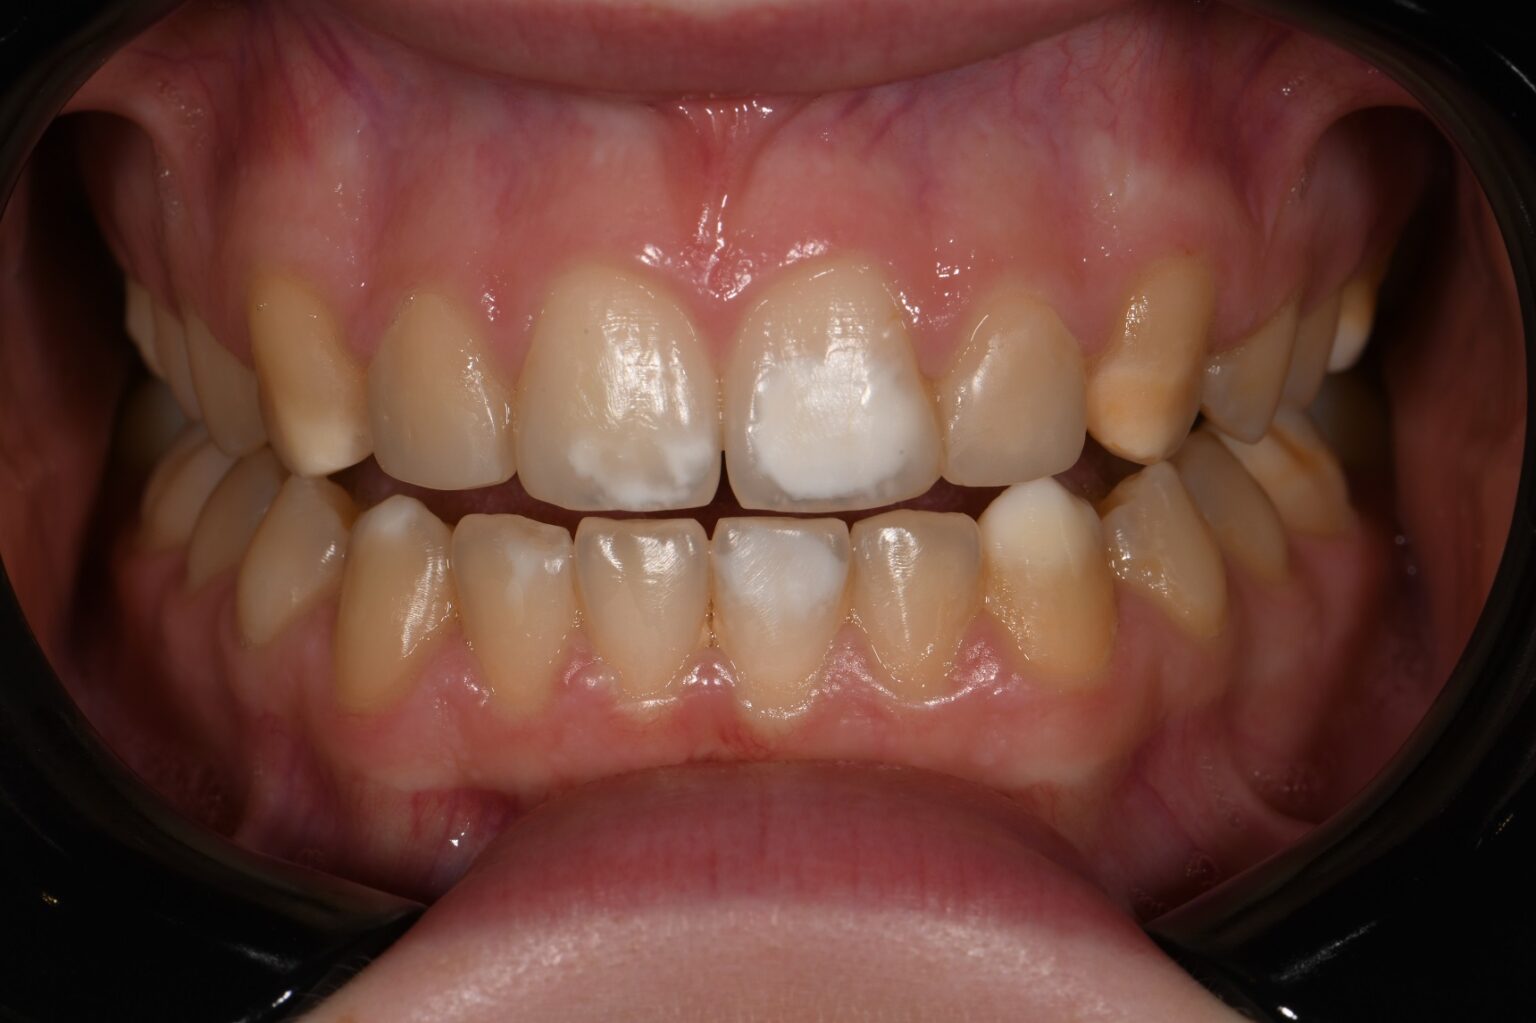

From smiledentallounge.com

ICON Resin Infiltration The Smile Dental Lounge Dental Clinic Johor Where Is Resin Infiltration Most Successfully Used They were informed that the process may need to be repeated several times in order to treat deeper lesions. resin infiltration is a minimally invasive technique to treat mild hypomineralized lesions. the principle of resin infiltration is to perfuse the porous enamel with resin by capillary action, thereby arresting lesion. resin infiltration seems to be a clinically. Where Is Resin Infiltration Most Successfully Used.